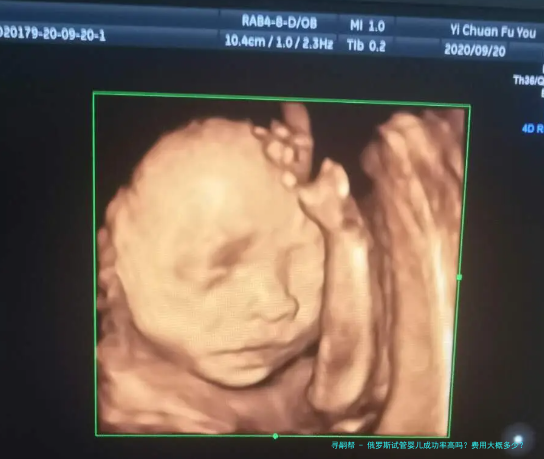

俄罗斯试管婴儿成功率高吗?费用大概多少?攻略全解析

在俄罗斯进行三代试管婴儿的相关攻略和费用关键是此刻很多面临生育困扰的家庭所注意的热点。数据统计显示,俄罗斯的试管婴儿技术在成功率上症状卓越,且相较对于其他,其费用也显得较为亲民。全体而言,进行三代试管婴儿的有关费用大约在2500至5000美元之间。